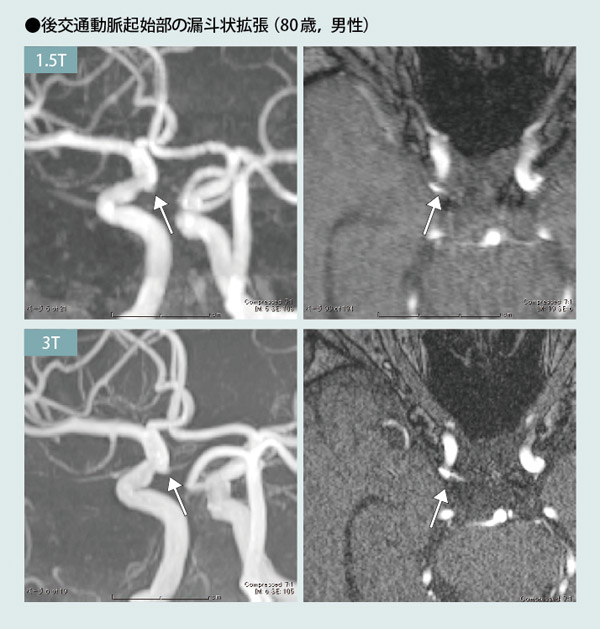

IC-PC動脈瘤との鑑別がしばしば問題となるのが漏斗状拡張 infundibular dilatation です。 鑑別のポイントは ▷漏斗状拡張は先端から動脈分枝が出ている→MIP像やMPR画像を作成▷動脈瘤は後外側下方に向かい、漏斗状拡張は先端部が内側向きに出ることが多い。 という点です。

tim e-of -fl i ght MR angio gr aph y Tim e- of-f li ght MR angio gra ph yat 3T - ex perime ntal tes tin g and cl i。

脳動脈瘤の画像診断と撮影法ー破裂リスクの評価と漏斗状拡張との鑑別。